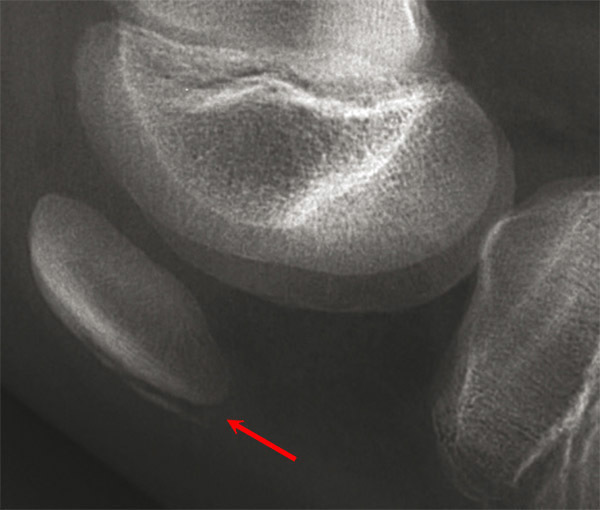

Ostéochondrose apophysaire de la rotule associant un aspect fragmenté de sa pointe, et un double contour de la moitié inférieure (maladie de Sinding-Larsen). Voir : P. Journeau, E. Polirzstok, F. Launay, D. Barbier. Lésions osseuses de sollicitation excessive chez l’enfant sportif. Rev Prat 2015;65(8);1084-90.